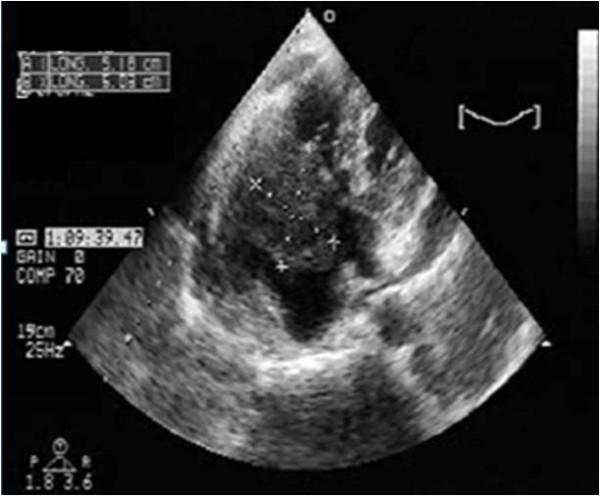

We report the case of a 64-year-old non-immunodeficient Caucasian man, with cardiac tamponade and paroxysmal third-degree atrioventricular block. Echocardiography revealed the presence of a large pericardial effusion with signs of tamponade and a right ventricular mass was suspected. Scanner investigations clarified the sites, extension and anatomic details of myocardial and pericardial infiltration. Surgical resection was performed due to the rapid impairment of his cardiac function. Analysis of the pericardial fluid and histology confirmed the diagnosis of non-Hodgkin large B-cell lymphoma. He was treated with chemotherapy.

我们报告一例64岁非免疫缺陷的白种男性病例,该患者患有心脏压塞和阵发性三度房室传导阻滞。超声心动图显示存在大量心包积液并有压塞征象,怀疑有右心室肿块。扫描检查明确了心肌和心包浸润的部位、范围及解剖细节。由于其心功能迅速恶化,遂进行了手术切除。心包液分析和组织学检查确诊为非霍奇金大B细胞淋巴瘤。他接受了化疗。